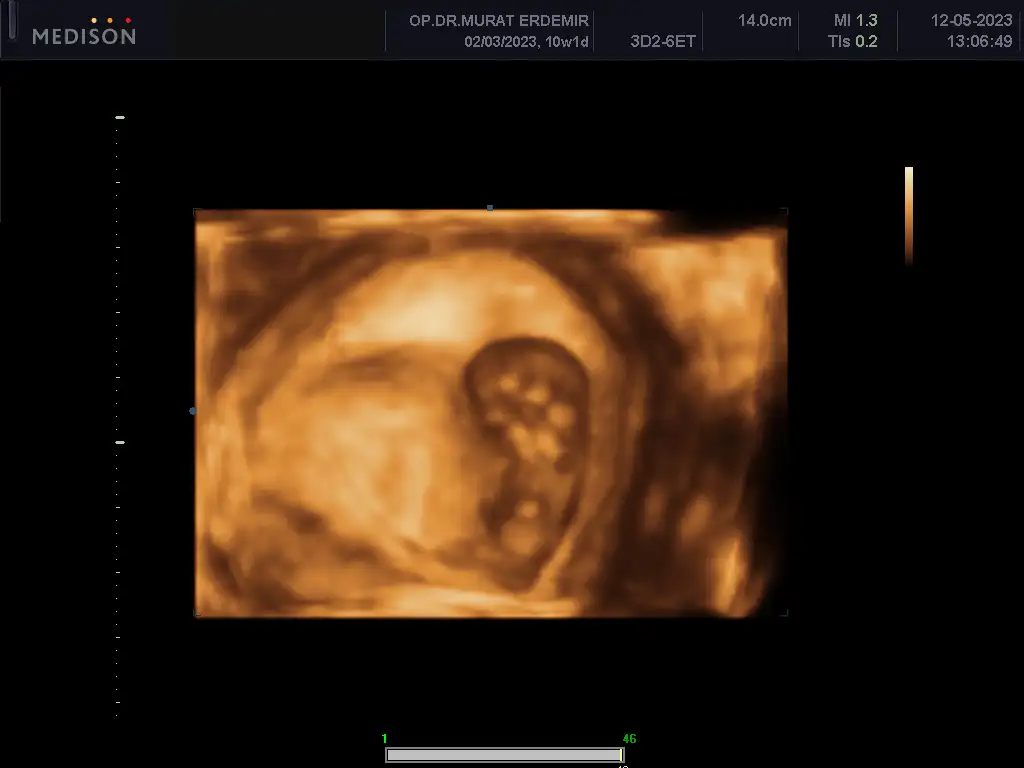

Bu arada son ultrason videosundan bir kesit gönderiyorum. Nub u şu altta görünen sanırım bizim oğlanın 😃 karşıya doğru uzayan şey sanırım ama bilemedim

Eklentiler

• IMG_8288.webp

IMG_8288.webp

12,9 KB · Görüntüleme: 84